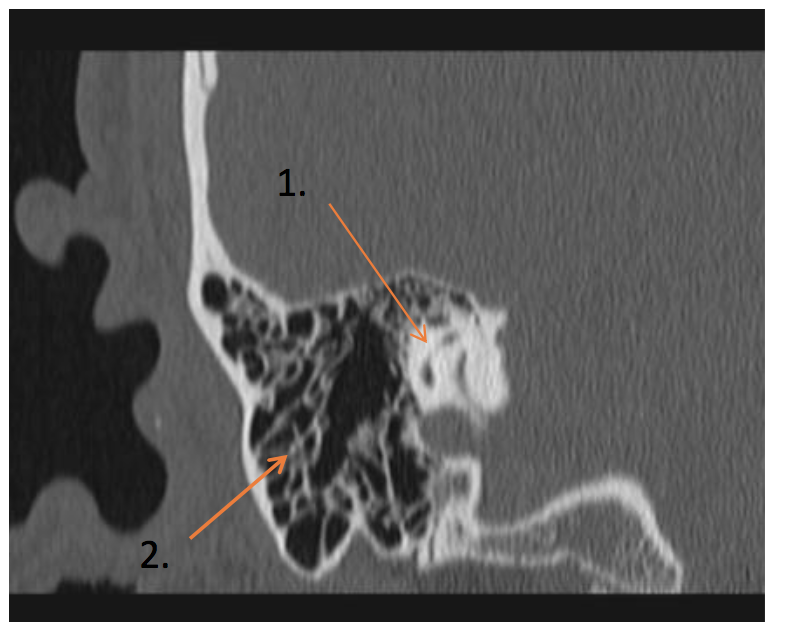

What are the labels in the image

• 1 = Lateral Semicircular Canal

What are the labeled images